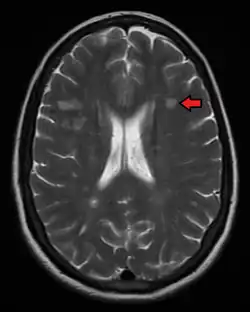

Multiple sclerosis as seen on MRI

Multiple sclerosis is typically diagnosed based on the presenting signs and symptoms, in combination with supporting medical imaging and laboratory testing.[5] It can be difficult to confirm, especially early on, since the signs and symptoms may be similar to those of other medical problems.[1][90]

Magnetic resonance imaging (MRI) of the brain and spine may show areas of demyelination (lesions or plaques). Gadolinium can be administered intravenously as a contrast agent to highlight active plaques, and by elimination, demonstrate the existence of historical lesions not associated with symptoms at the moment of the evaluation.[94][95]

Central vein signs (CVSs) have been proposed as a good indicator of MS in comparison with other conditions causing white lesions.[96][97][98][99] One small study found fewer CVSs in older and hypertensive people.[100] Further research on CVS as a biomarker for MS is ongoing.[101]